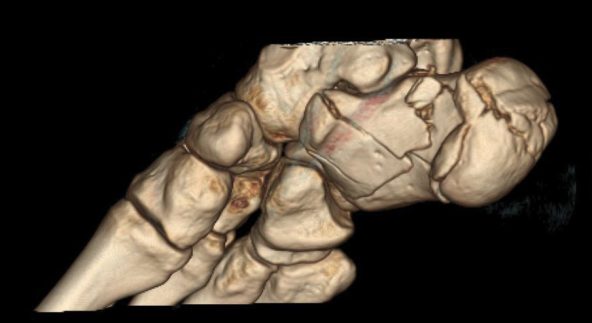

Lesiones, bien agudas o crónicas, que afectan a los huesos, articulaciones, ligamentos o músculos, y cuyo tratamiento definitivo, generalmente, es quirúrgico.